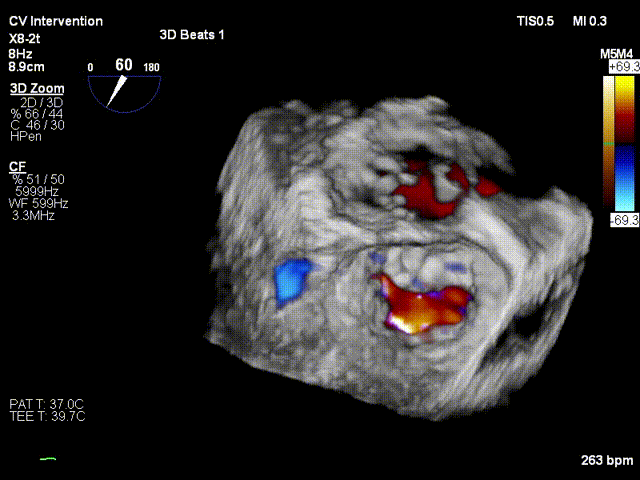

术前3D view提示:二尖瓣重度反流

术后3D view提示:二尖瓣反流显著减少